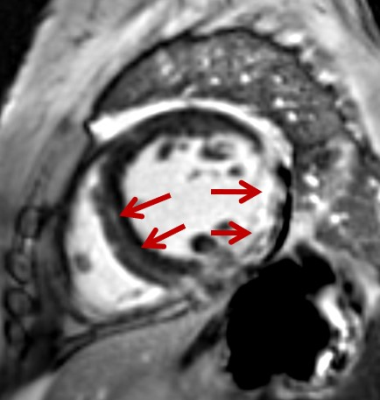

A 56-year-old woman with systemic lupus erhythematosus. Late gadolinium enhancement image showed endocardial contrast in in lateral wall and posterior wall of the left ventricle.